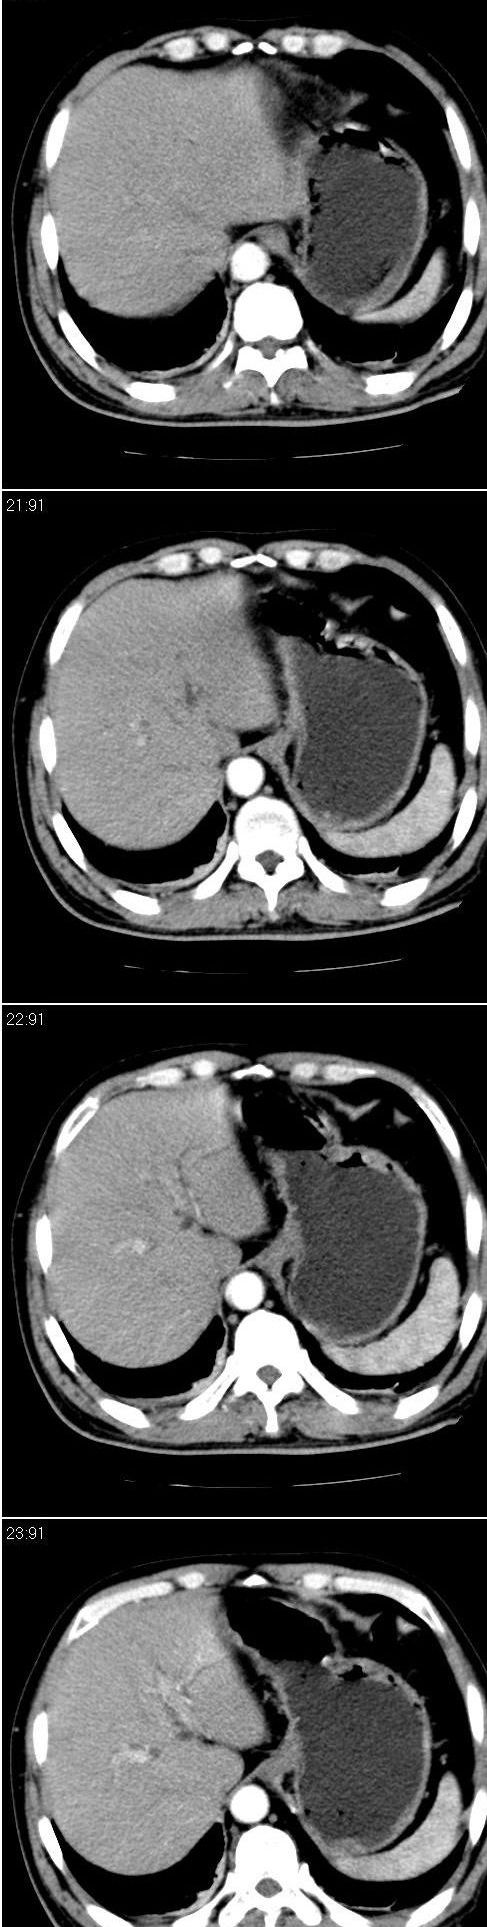

标题: CT13147:男,57岁。因胆结石阻塞性黄疸入院。 [打印本页]

标题: CT13147:男,57岁。因胆结石阻塞性黄疸入院。

男,57岁。因胆结石阻塞性黄疸入院。这是胆囊切除术后的照片,看看此片到底有什么问题。

单纯胆囊切除术后改变,腹壁可见引流管影,楼主有何高见?

胆总管有没有问题,尤其是肝门附近的胆总管?

肝门附近的胆总管轻度扩张 请楼主复习术前片

肝内外胆管轻度扩张,胆囊窝内见引流管考虑胆囊切除术后改变.胃窦部软组织似增厚,建议胃镜检查.

在手术切除胆囊的过程中,发现肝门部胆总管恶性占位,因为家属不同意手术,没有切除,能看出来么?

现有资料很难说,薄层可能清楚些,如临床不提供,易诊断为术后改变。

不是楼主提醒还真看不出来,肝内胆管扩张。略显僵硬。

肝内外胆管轻度扩张。楼主提示左右肝管合汇区域壁稍厚。胆总管末段壁似也稍厚有轻度强化。就现有资料诊断难。